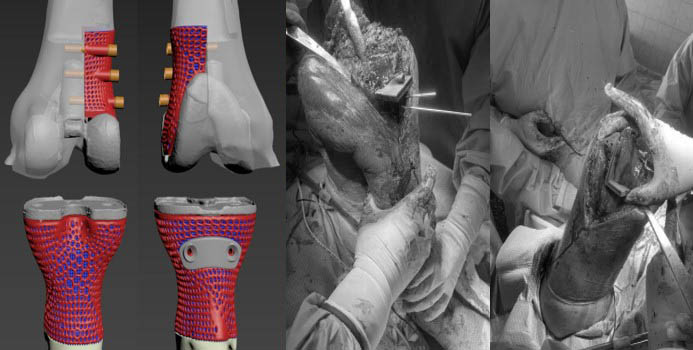

Етапи проектування індивідуальних аугументів для ревізійного ендопротезування колінного суглоба

Паціент М., Міно-вибухове поранення кісток колінного суглобу. Мегадефекти стегнової та Великогомілкової кістки 3 ст по класифікації (Aori). остіоміеліт. Стан після заміщення дефектів спейсером з антибіотиком

Виконане операційне втручання: Видалено спейсери з антибіотиком, резекція за допомогою індивідуальних навігаційних систем та імплантовано ендопротез з індивідуальними аугментами